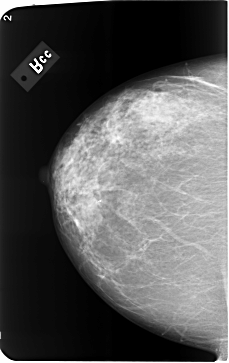

B_3493_1.LEFT_CC

LEFT_CC LINES 5776 PIXELS_PER_LINE 3672 BITS_PER_PIXEL 12 RESOLUTION 50 OVERLAY

FILE: B_3493_1.LEFT_CC.OVERLAY

TOTAL_ABNORMALITIES 1

ABNORMALITY 1

LESION_TYPE CALCIFICATION TYPE PLEOMORPHIC DISTRIBUTION CLUSTERED

ASSESSMENT 4

SUBTLETY 3

PATHOLOGY BENIGN

TOTAL_OUTLINES 1

BOUNDARY